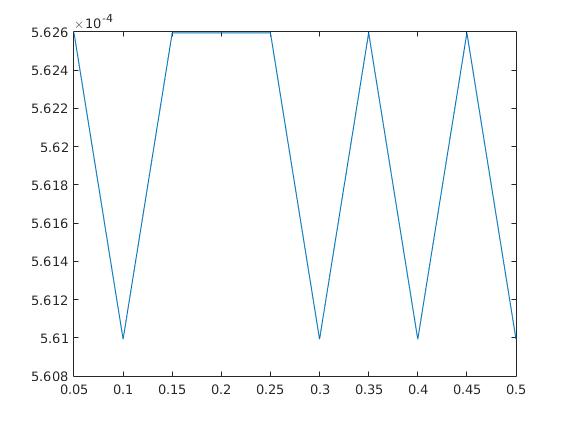

The parameters , and were optimized by comparing the final results with the existing ground truth in both cases. Here we mention that the choice of parameters is not a trivial task, since the result strongly varies with a change in the parameters. In figure 5, the scaling between the error in the -norm between exact and reconstructed image sequence per pixel per time step and the choice of each parameter out of a certain range is displayed examplarily for the heart data set. Here, we chose , and and kept two parameters fixed while plotting the error in the third one. The adaption of parameters in case of real data and, if possible, the elimination of some of them remains a future task.